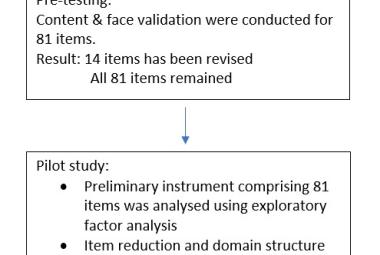

One of the notable complications of impacted mandibular third molar (MTM) is distal caries of the mandibular second molar (MSM) which can eventually lead to its early loss. The present study aimed to investigate the incidence of dental caries in MSM associated with impacted MTM and to propose an assessment protocol for MTM management. Patients’ dental records with dental panoramic tomography (DPT) imaging were studied retrospectively, in total 583 MTM images were evaluated. The presence of MSM distal caries, patient’s details, impaction depth, pattern and angulation of MTM and the distances between distal MSM and mesial MTM were assessed. Logistic regression analysis was performed on the data set. The highest caries incidence was observed in mesioangular impacted MTM (34.1%). Majority of the caries found were Level A (27.9%) and Class II (27.0%). The highest distance between distal MSM and MTM contributing to caries was 0.70-0.99 cm (31.9%). Patients’ age, angulation, pattern and depth of impacted MTM are the predictors which significantly increase the caries incidence in MSM (p<0.05). Prophylactic removal of MTM should be proposed when the distance of mesial impacted MTM and distal MSM is around 0.70-0.99 cm, and is mesially angulated with IIA classification.

Salah satu komplikasi ketara gigi geraham bongsu rahang bawah (MTM) yang tidak tumbuh sepenuhnya (terimpak) ialah karies distal pada geraham kedua rahang bawah (MSM) yang akhirnya boleh menyebabkan kehilangan awal gigi tersebut. Kajian ini bertujuan untuk menyiasat kejadian karies gigi pada MSM yang mempunyai kaitan dengan MTM terimpak serta cadangan penilaian langkah pengurusan berkaitan dengan MTM. Rekod pergigian pesakit bersama gambar panoramik pergigian telah dikaji secara retrospektif, dengan sejumlah 583 imej MTM telah dinilai. Kewujudan karies distal MSM, butiran pesakit, kedalaman impaksi, corak dan sudut MTM serta jarak antara MSM distal dan MTM mesial telah dinilai. Analisis regresi logistik dijalankan ke atas set data. Insiden karies tertinggi diperhatikan pada MTM terimpak mesioangular (34.1%). Kebanyakan karies yang ditemui ialah Tahap A (27.9%) dan Kelas II (27.0%). Jarak tertinggi antara MSM distal dan MTM yang menyumbang kepada karies ialah 0.70-0.99 cm (31.9%). Umur pesakit, sudut, corak dan kedalaman MTM terimpak ialah pembolehubah yang meningkatkan insiden karies pada MSM secara signifikan (p<0.05). Cabutan pencegahan gigi MTM sepatutnya dicadangkan apabila jarak antara MTM terimpak mesial dan MSM distal adalah sekitar 0.70-0.99 cm, dan MTM bersudut mesial dengan klasifikasi IIA.